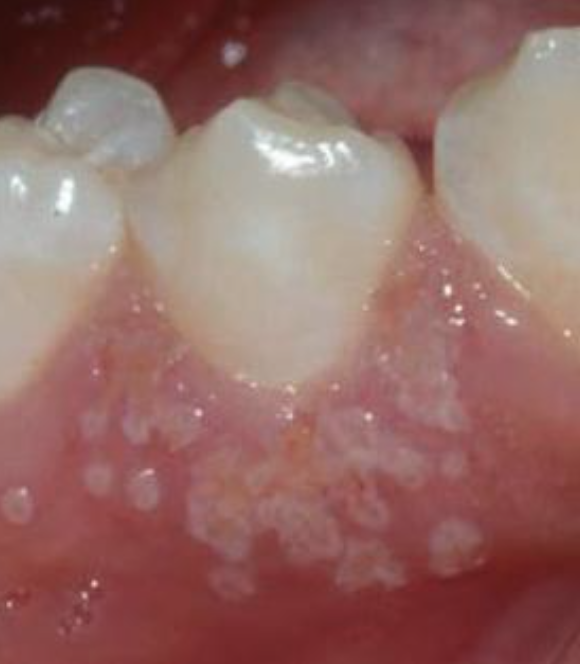

gingival abscess

localized purulent infection that involves the marginal gingiva or interdental papilla

etiology: acute inflammatory response to foreign substances forced into the gingiva

clinical features: localized swelling LIMITED to marginal gingiva or papilla. A red, smooth, shiny surface. May be painful and appear pointed. Purulent exudate may be present. No previous periodontal disease.